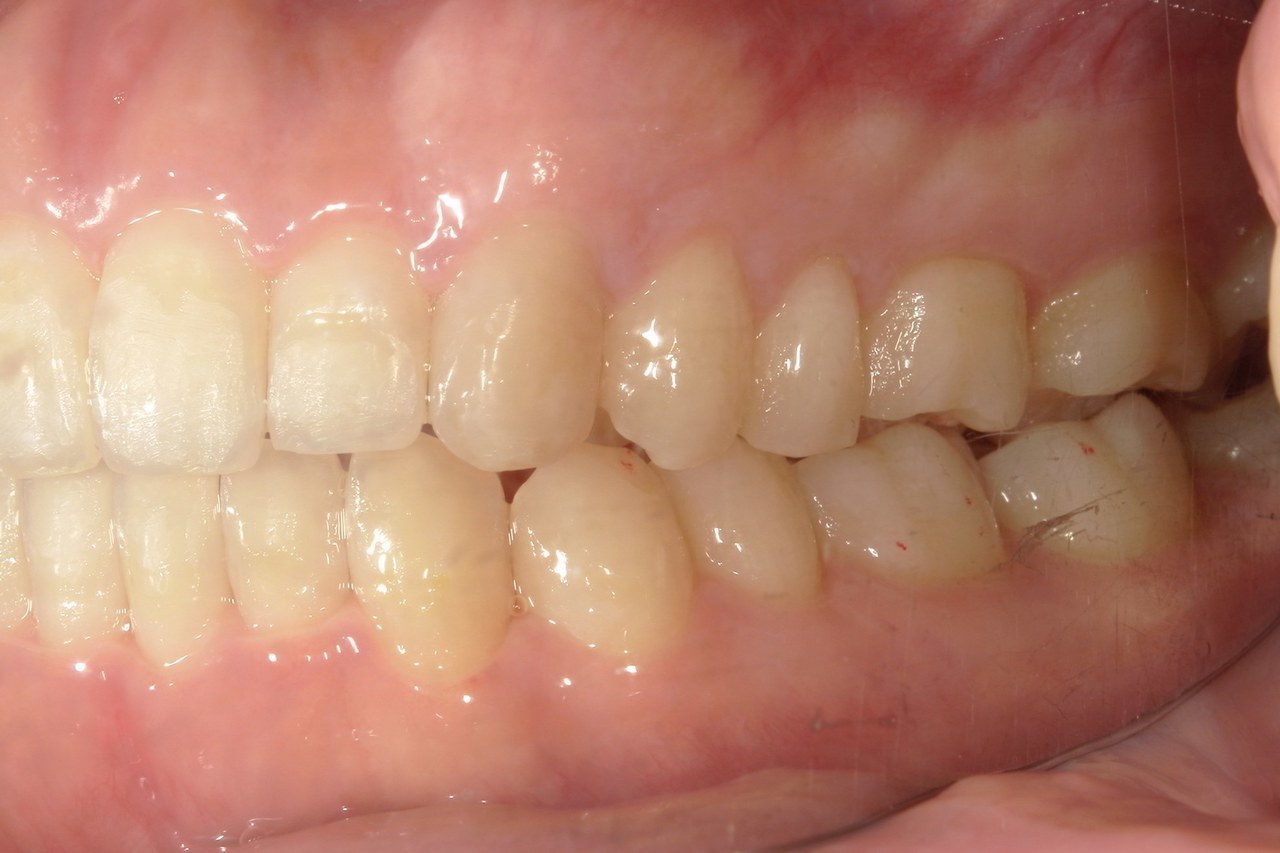

Before

浜松市中央区・自動車学校前駅のインビザラインの症例

Y.S. 30代男性

全体的にガタガタしているのが気になるという主訴だったため、上下左右第一小臼歯を抜歯し、叢生を並べました。

治療の期間:R3. 9/1〜R5. 10/31

治療の価格:88万円